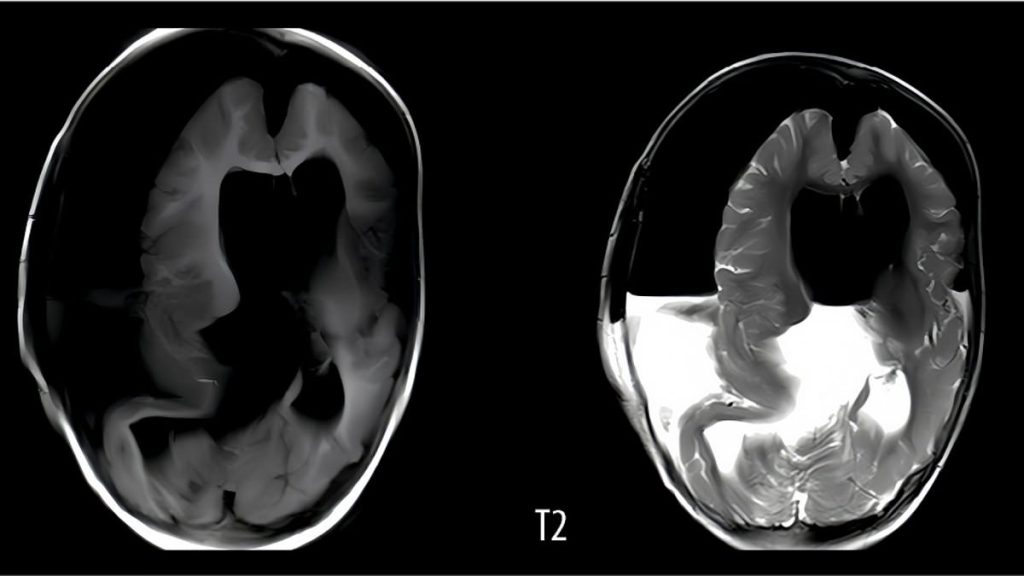

So the doctor scanned her head, They found a mass inside the skull that was 5 inches in diameter (13 centimeters), a little bigger than a baseball, with a long chunk of bone embedded within it.

Inside they found a white capsule containing a thick brown liquid and an immature fetus.

The fetus had a spine, bones, a mouth, eyes, hair, forearms, hands and the beginnings of feet. It was 18 centimetres long.

This caused “severe brain tissue compression.” The patient never woke up and remained on life support after the operation, suffering from seizures.